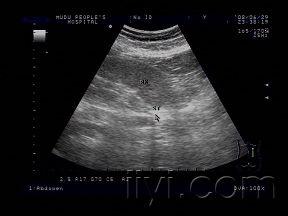

双侧输尿管结石 超声医学讨论版 爱爱医医学论坛

寻找输尿管结石的个人经验和方法 超声医学讨论版 爱爱医医学论坛

临床必备肾结石输尿管结石超声表现一览

今天做的一例输尿管末端结石 超声医学讨论版 爱爱医医学论坛